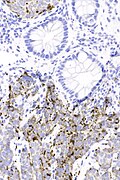

PSAP - intermed. mag.

- Cytoplasmic staining.